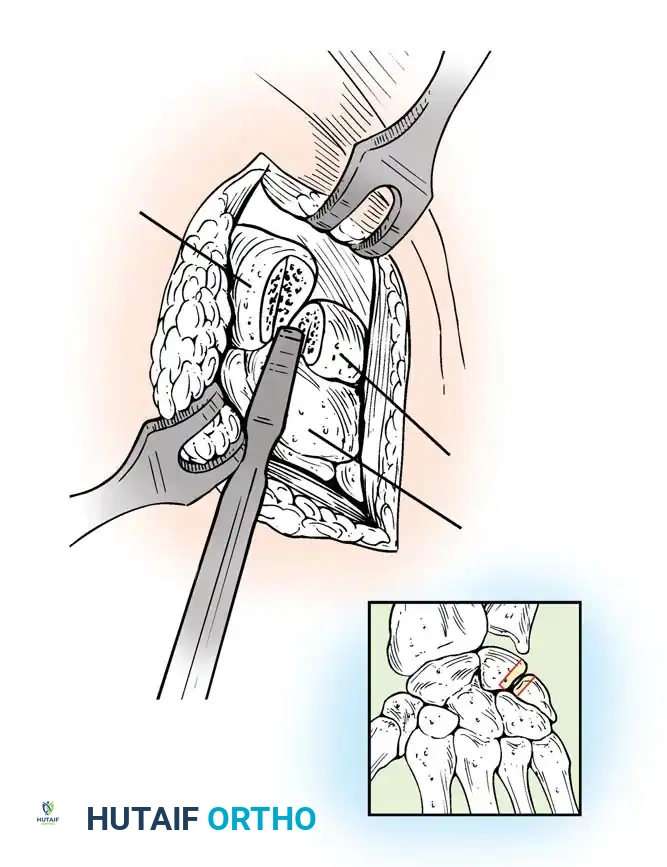

- Exposure: The extensor retinaculum is elevated, and the extensor pollicis longus (EPL) is transposed radially. The dorsal capsule is excised to expose the radiocarpal and midcarpal joints.

- Joint Preparation: The dorsal cartilage of the radiocarpal, intercarpal, and third carpometacarpal joints is meticulously denuded down to bleeding subchondral bone.

- Bone Grafting: A local distal radial bone graft portal is utilized. Cancellous bone is harvested from the distal radius metaphysis to augment the fusion sites.